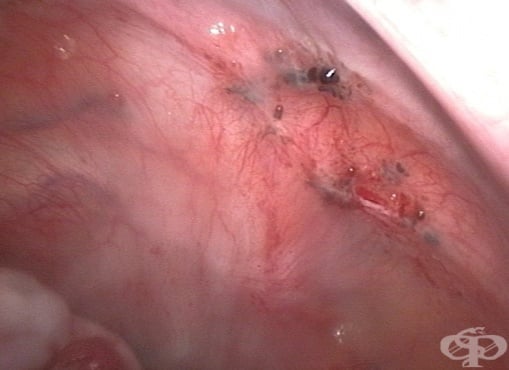

Ендометриоза Ендометриоза Симптоми на ендометриоза Симптоми на ендометриоза Ендометриоза Стадий 1 Стадий 2 Стадий 3 Стадий 4 Ехография - шоколадова киста (ендометриома) Лапароскопия на ендометриоза Лапароскопия на ендометриоза Хиатологично изследване на ендометриоза Ендометриоза на десния яйчник Аденомиоза на матката Ендометриоза и аденомиоза

ЕндометриозаЕндометриозаСимптоми на ендометриозаСимптоми на ендометриозаЕндометриозаСтадий 1Стадий 2Стадий 3Стадий 4Ехография - шоколадова киста (ендометриома)Лапароскопия на ендометриозаЛапароскопия на ендометриозаХиатологично изследване на ендометриозаЕндометриоза на десния яйчникАденомиоза на маткатаЕндометриоза и аденомиоза Ендометриоза